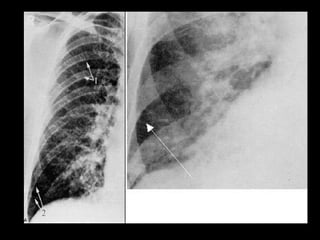

Infiltrado en alas de mariposa ó de murciélago, por edema pulmonar . Líneas B de Kerley .

Infiltrado en alasde mariposa ó de murciélago, por edema pulmonar . Líneas B de Kerley .